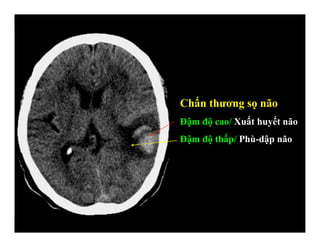

Chấn thương sọ não

Đậm độ cao/ Xuất huyết não

Đậm độ thấp/ Phù-dập não

CÁC TỪ DIỄN TẢ ĐẬM ĐỘ

Giảm đậm độ (Hypodense)

Đồng đậm độ (Isodense)

Tăng đậm độ (Hyperdense).